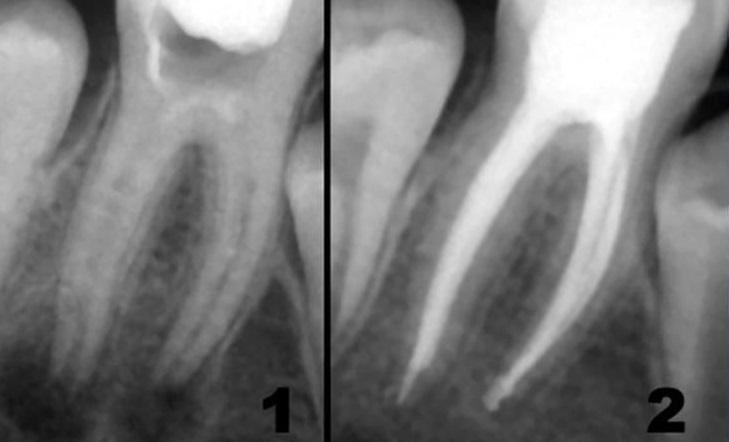

Стоматологические Исследования: Рентген Инвагинации Зубов